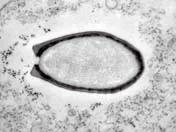

▲法國(guó)科學(xué)家復(fù)活的一種在西伯利亞永久凍土中冷凍了3萬(wàn)多年的巨型無(wú)害病毒

2014年3月,科學(xué)家在俄羅斯的西伯利亞凍土層中發(fā)現(xiàn)了迄今世界上最大的巨型病毒,長(zhǎng)達(dá)1.5微米,科學(xué)家將其命名為“西伯利亞闊口罐病毒”。